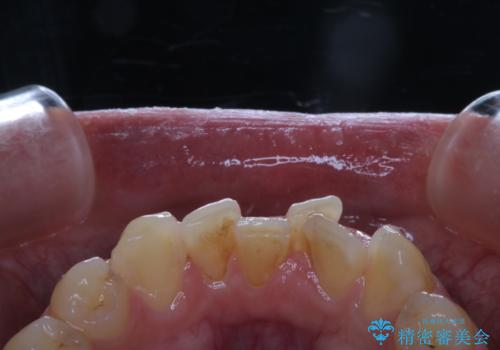

前歯メインにステインの付着が見られ、コース内容を相談した結果PMTC(保険外治療)の30分コースを行いました。